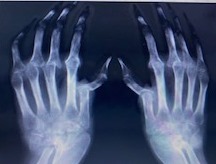

Рис. 12. Выраженное симметричное сужение суставных щелей, множественные кистовидные просветления костной ткани и эрозии в пястно-фаланговых суставах

Эрозии суставов. Наличие эрозий суставных поверхностей — наиболее характерный для полиартрита рентгенологический симптом (рис. 15). Появление эрозий связано с разрушением субхондральной замыкательной пластины и участка губчатой кости эпифиза сустава. Различают 3 типа костных эрозий. Краевые поверхностные эрозии выявляют в тех местах внутрисуставного участка кости, где обычно кость не защищена покрывающим сустав хрящом (рис. 16—19). Именно эти «оголенные» участки эпифизов костей на краях суставных поверхностей первыми подвергаются «атакам» активно пролиферирующей синовиальной оболочки сустава. Компрессионные эрозии имеют место в том случае, когда происходит провал (коллапс) субхондральной части губчатой кости на фоне околосуставного остеопороза, кистовидной перестройки костной структуры, что приводит к инвагинации суставной поверхности внутрь эпифиза (рис. 20, 21). Данные изменения обнаруживаются в суставах, подверженных большим мышечным нагрузкам и движениям, чаще всего это тазобедренный сустав, суставная поверхность головки бедренной кости.

По выраженности различают поверхностные и глубокие эрозии, по количеству — единичные и множественные. Активно формирующиеся эрозии имеют острые края и нечеткие границы, для «старых» эрозий характерны закругленные края и склеротическое основание.

Стадия 2. Умеренный (выраженный) околосуставный остеопороз. Множественные кистовидные просветления костной ткани. Немногочисленные или (множественные) разной степени выраженности сужения суставных щелей. Единичные эрозии (1—4) суставных поверхностей. Небольшие деформации костей.

Стадия 3. Умеренный (выраженный) околосуставный остеопороз. Множественные кистовидные просветления костной ткани. Множественные выраженные сужения суставных щелей. Множественые эрозии суставных поверхностей (5 и более). Множественные умеренные (выраженные) деформации костей. Подвывихи и вывихи суставов.